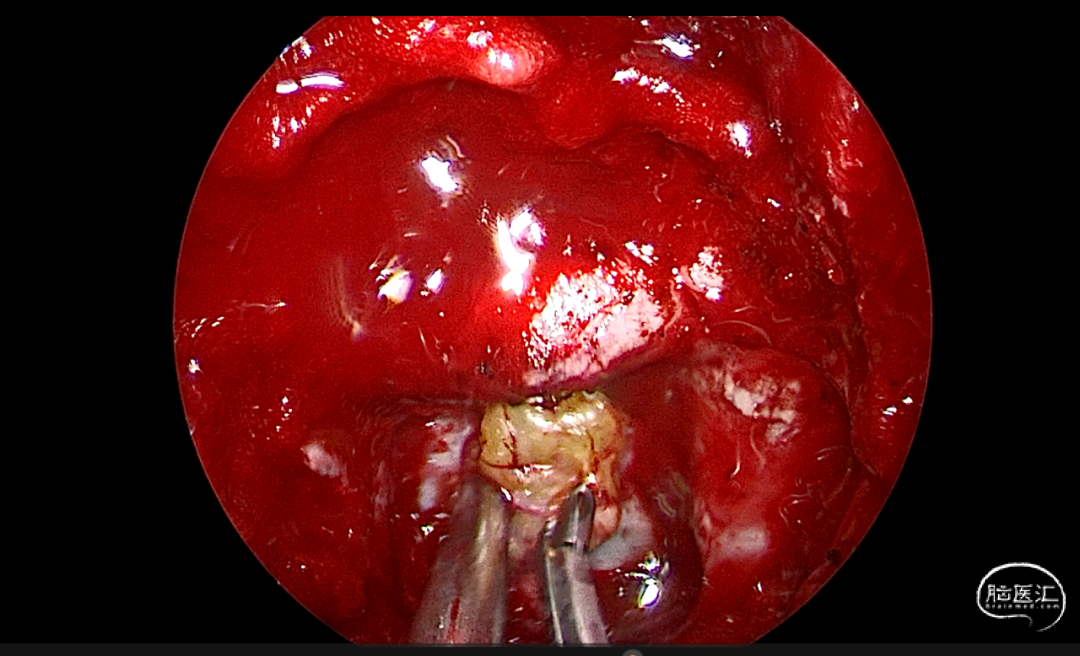

手术照片

带蒂粘膜瓣修复